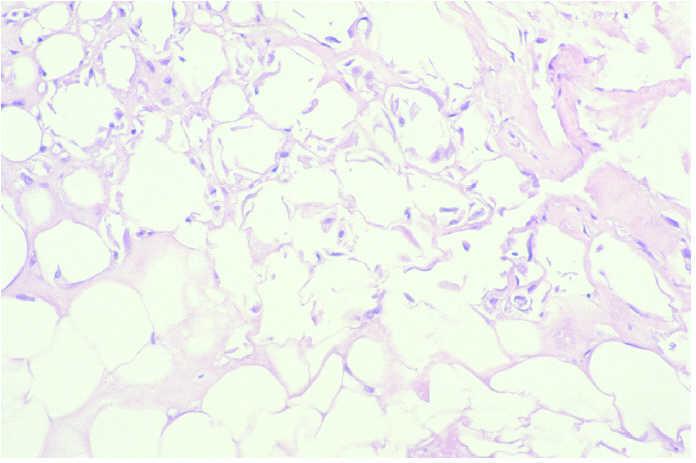

En el caso que fue biopsiado precozmente, pudo detectarse en la porción superficial necrosis epidérmica y de las glándulas ecrinas sin infiltrado inflamatorio acompañante. Así mismo, se encontró trombosis masiva de los vasos dérmicos superficiales y profundos (fig. 4). En el tejido celular subcutáneo pudo verse necrosis de los adipocitos cercanos al septo, así como paniculitis de predominio septal, escasamente celular.

Fig. 4.--Necrosis epidérmica y de las glándulas ecrinas sin infiltrado inflamatorio acompañante. Trombosis masiva de los vasos dérmicos superficiales y profundos. (Hematoxilina-eosina, ×10.)

Los resultados de la revisión histológica permiten concluir que los hallazgos histológicos dependen del momento en el que se efectúa la biopsia y no del fármaco extravasado. Así pues, en fases precoces (primera semana tras el accidente de extravasación), se aprecia trombosis en los vasos de mediano calibre de dermis y del tejido celular subcutáneo, junto a edema dérmico y necrosis epidérmica en grado variable. En el tejido celular subcutáneo se encuentra una paniculitis septal acompañada de un infiltrado inflamatorio escasamente celular de predominio linfocitario y abundante necrosis de adipocitos.